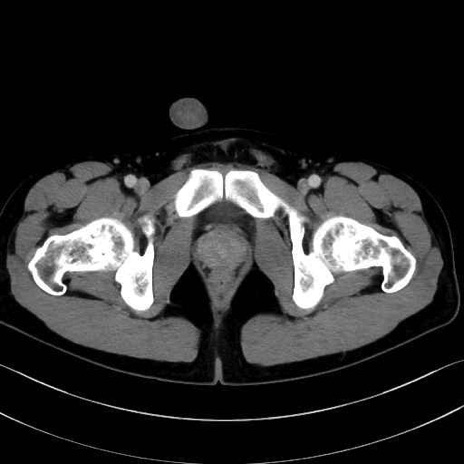

精嚢(seminal vesicle)のCT画像における解剖

症例

【症例】20歳代 男性 スクリーニング